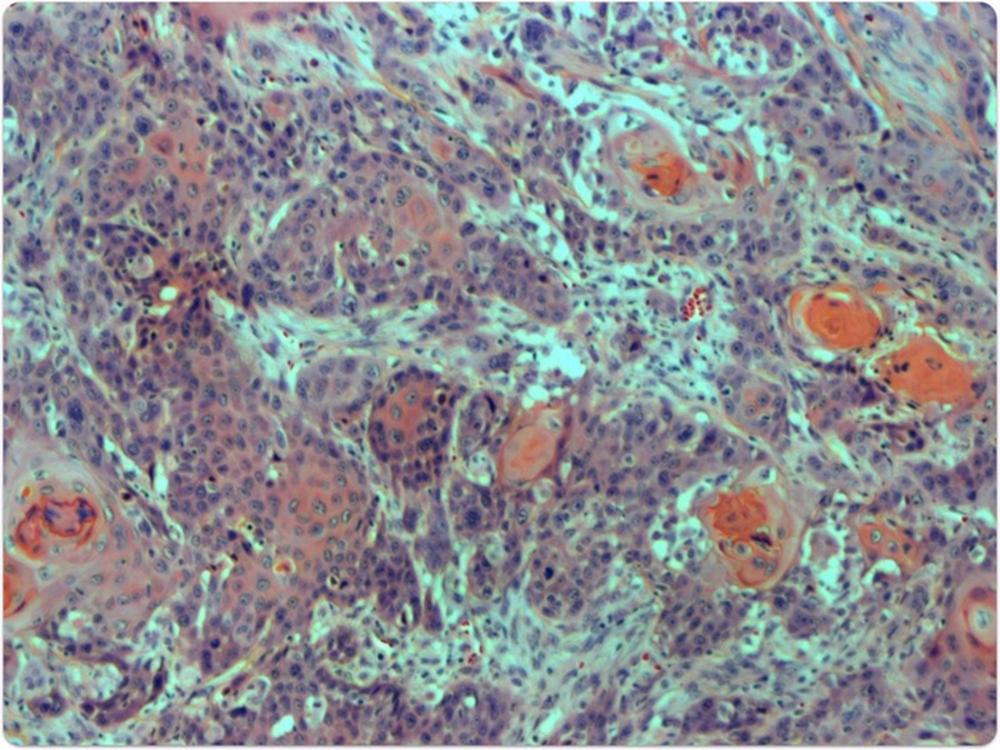

Las personas que nacen con anemia de Fanconi pueden sufrir numerosos problemas médicos, como insuficiencia de la médula ósea, malformaciones congénitas y un mayor riesgo de padecer algunos tipos de cáncer, como el HNSCC, con tumores muy metastásicos que surgen en las mucosas de la boca, la nariz, la garganta o el esófago.

Para entender cómo la anemia de Fanconi puede estimular el desarrollo de estos tumores, estos investigadores analizaron tejidos tumorales de HNSCC aislados de más de 50 pacientes con anemia de Fanconi y los comparó con tumores de HNSCC extraídos de muestras de la población general. Tras secuenciar los genomas tumorales, descubrieron que las células tumorales con anemia de Fanconi presentaban a menudo genes con demasiadas o muy pocas copias.

Este fenómeno, conocido como variación en el número de copias, ya se había detectado en tumores de HNSCC de personas sin la enfermedad genética. Sin embargo, la diferencia entre los dos grupos era significativa: los pacientes con anemia de Fanconi presentaban muchas más variaciones en el número de copias de sus tumores que los individuos sin la enfermedad.

Estos hallazgos podrían explicar por qué los HNSCC de los pacientes con anemia de Fanconi tienden a ser especialmente mortales, con una supervivencia media de sólo 17 meses tras el diagnóstico.

La investigación también sugiere que las elevadas variaciones en el número de copias son el resultado de reordenamientos estructurales en los genomas de los pacientes con anemia de Fanconi que aparecen cuando las células no reparan adecuadamente el ADN dañado por aldehídos durante la división celular. Los científicos observaron que los tumores de estos pacientes presentaban con frecuencia estas variantes estructurales, con tramos de ADN que aparecían en lugares erróneos o que se perdían por completo.